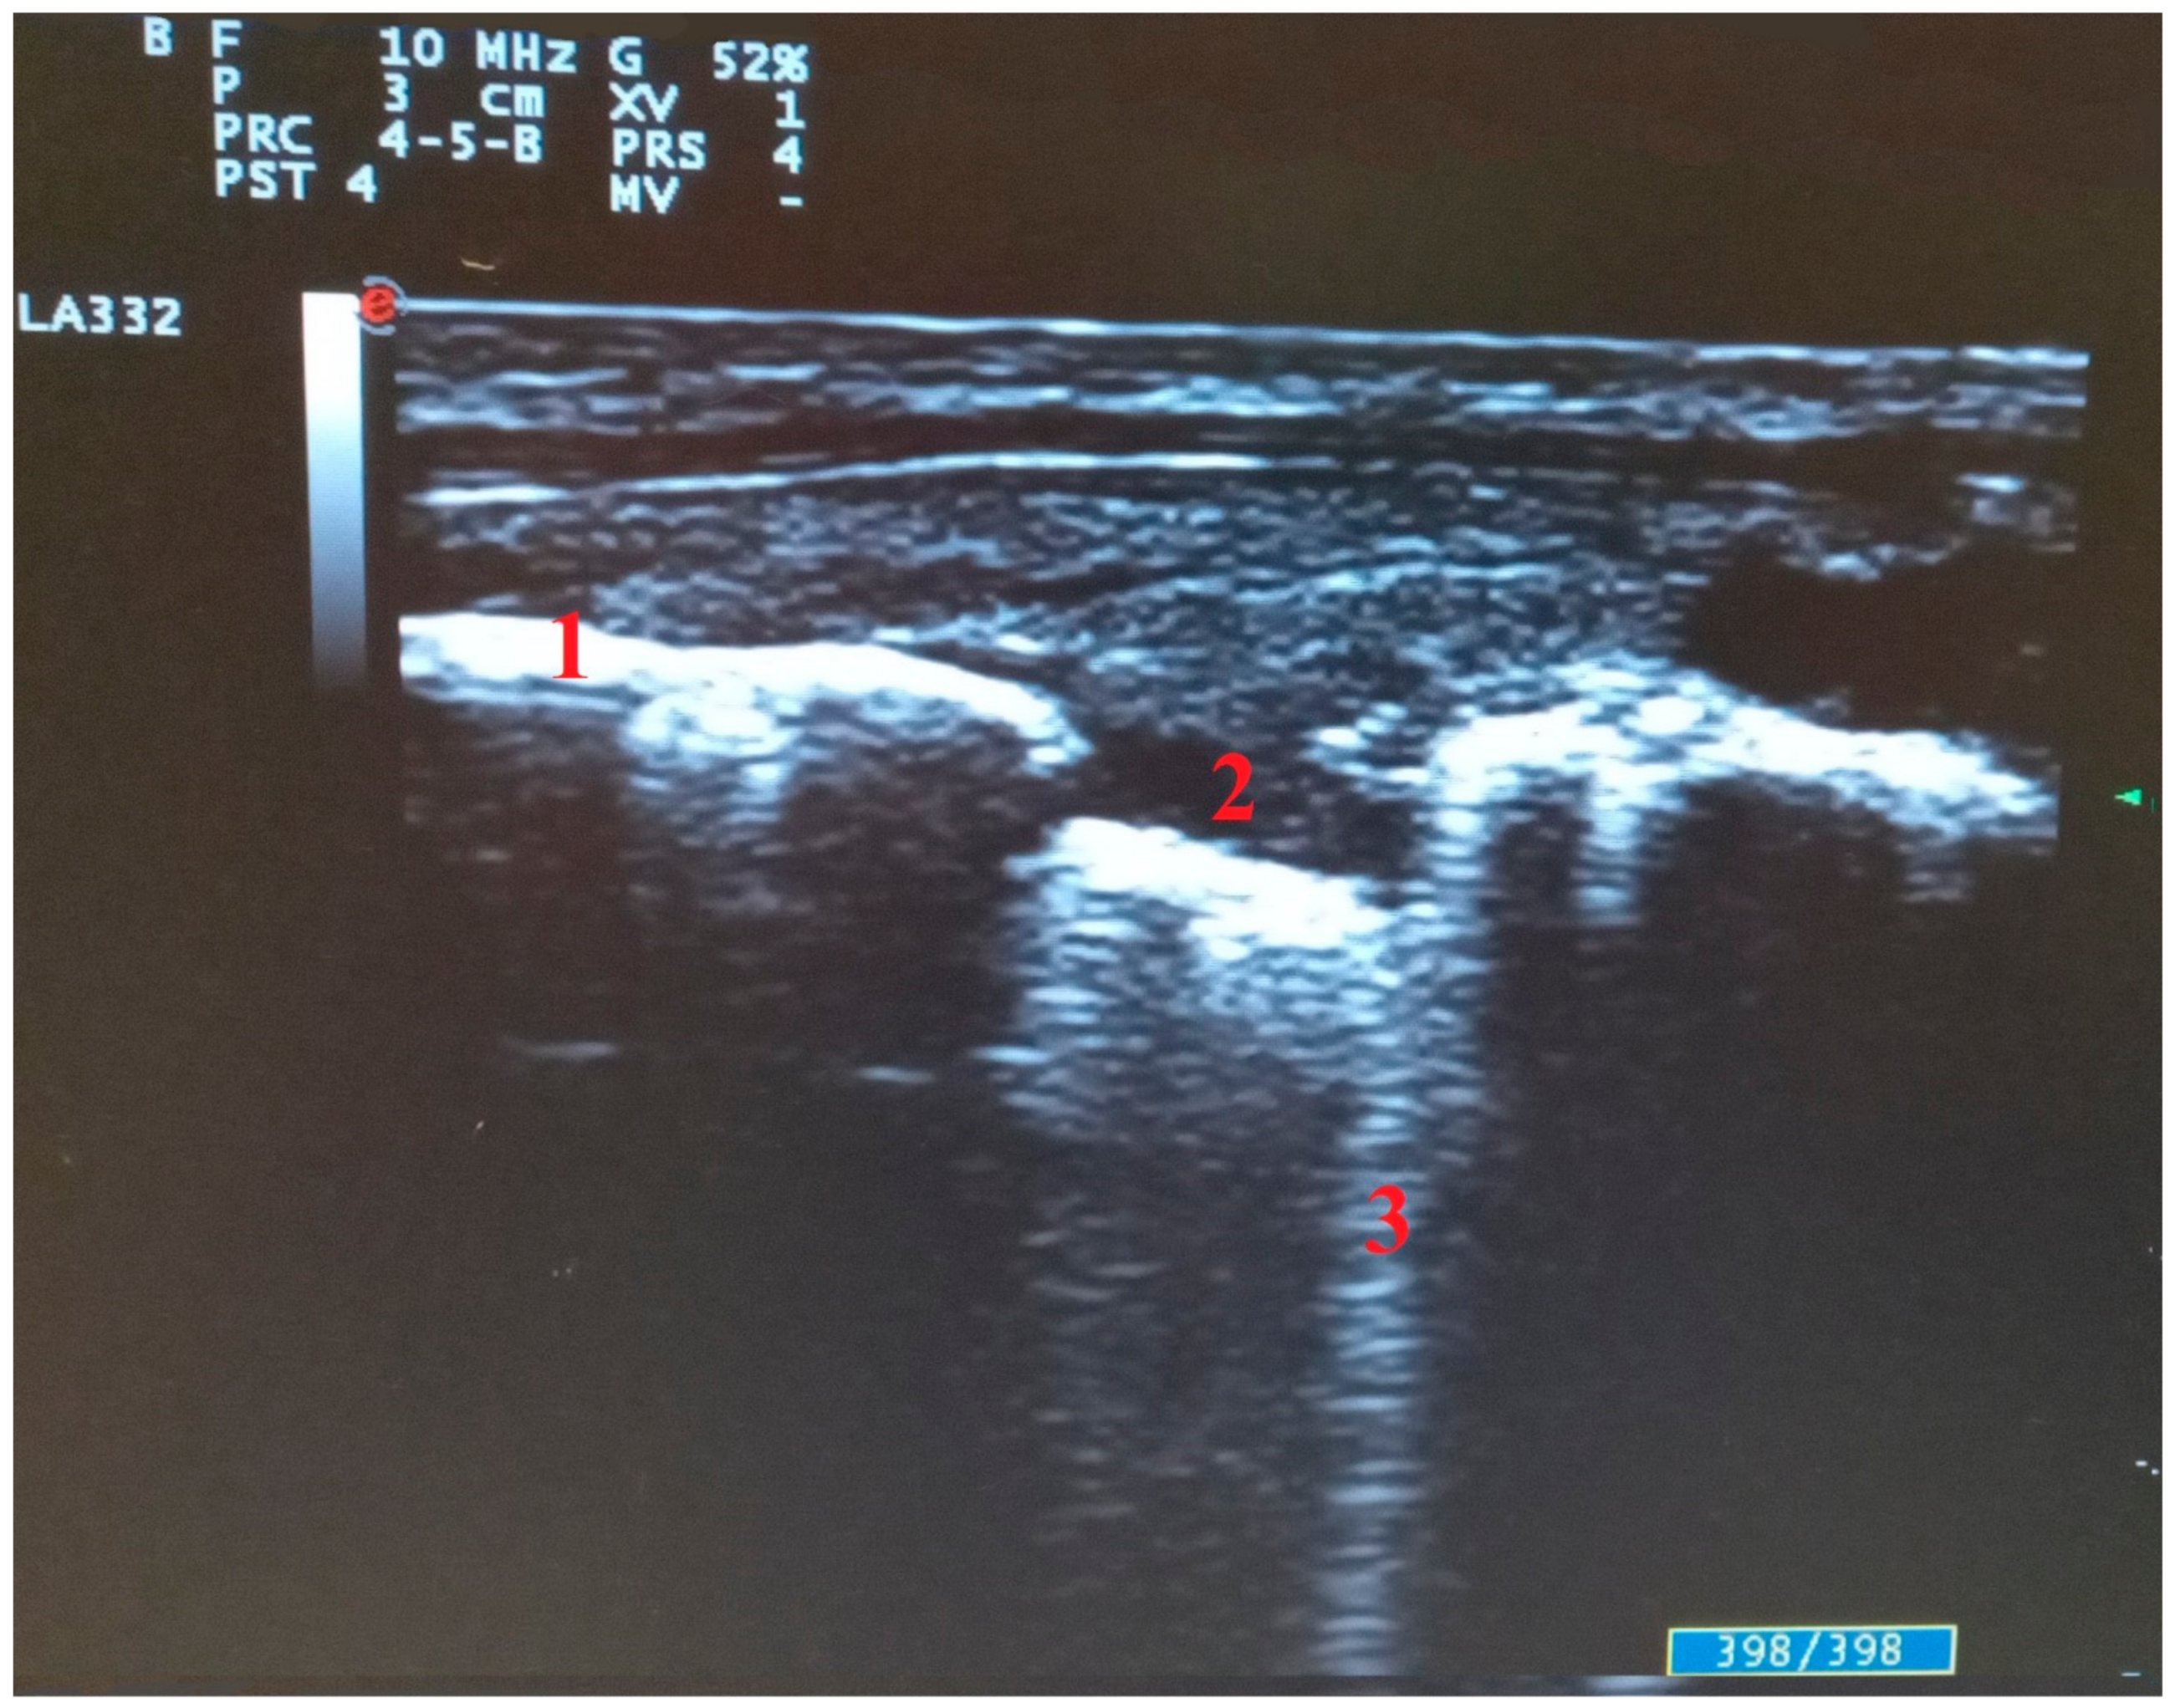

3. Lung Ultrasound in COVID-19 Pneumonia: Findings